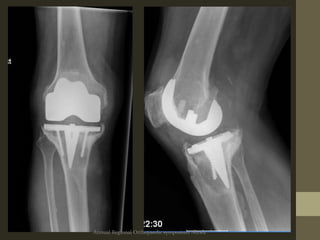

Diagnosis: Radiological

• Early Lysis/Lucencies

• Progressivelucent

lines

• Lytic area(s)

• Prosthesis position

• Stem movement

• Cortical perforation